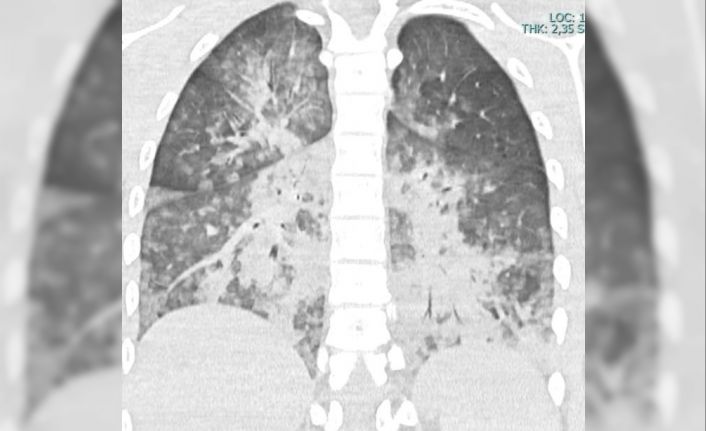

BOĞULMA VAKASI AKCİGER GÖRÜNTÜSÜ